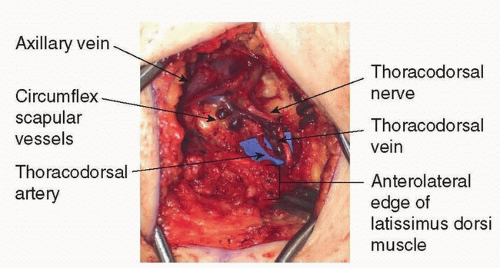

The thoracodorsal artery (TDA) and the circumflex scapular artery are the two main branches of the subscapular artery, which arises from the third division of the axillary artery (FIG 1).

The TDA travels along the lateral thoracic wall before diving into the latissimus dorsi muscle about 9 from its origin. Prior to its entry into the muscle, the TDA consistently (99%) gives off a branch to the serratus anterior muscle.4

The TD vessels are commonly divided for microvascular anastomosis just proximal to the serratus branch where the diameter of the artery is approximately 3 mm.5 Preservation of the serratus branch also allows for the use of a pedicled latissimus dorsi flap and an implant for breast reconstruction in case free tissue transfer is unsuccessful.

Proximally, there are often two veins that unify into a single TD vein. The TD vein travels with the TD artery and has an average diameter of 3.4 mm at its origin and 1.6 mm where it enters the latissimus dorsi muscle.6

The TD nerve enters the axilla deep to the axillary vein at a point several centimeters medial to the origin of the subscapular vessels. The nerve then continues toward the subscapular system and eventually travels parallel with the TD vessels along the lateral thoracic wall (FIG 2).